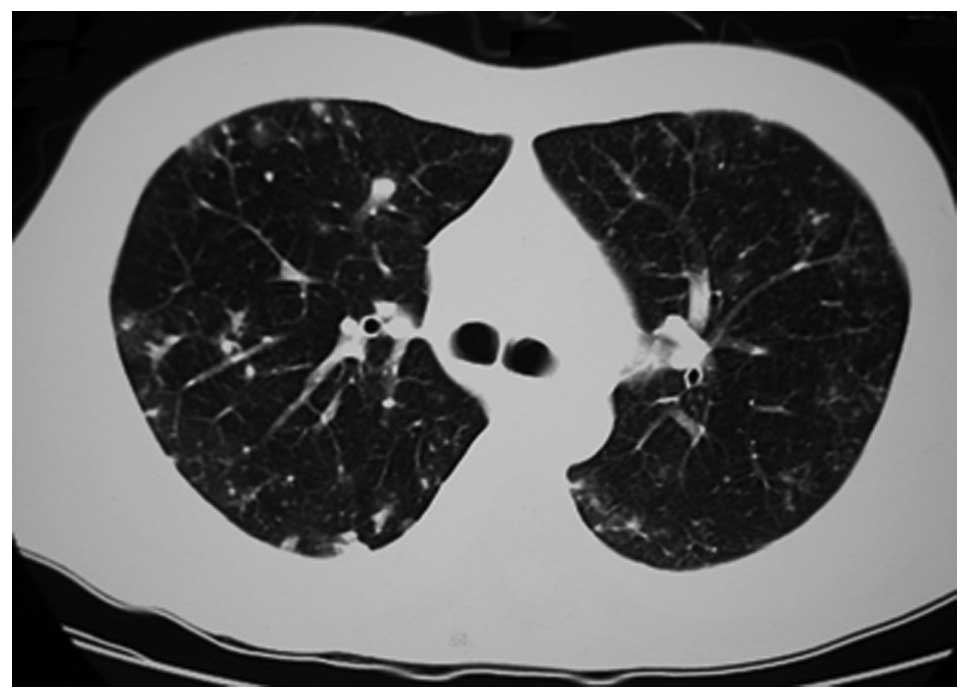

Treatment of pulmonary epithelioid hemangioendothelioma with combination chemotherapy: Report of three cases and review of the literature

No standard therapy for pulmonary epithelioid hemangioendothelioma (PEH) has yet been established due to the rarity of the disease, the lack of clear standards for treatment and the partial‑to‑complete spontaneous regression. This report describes three cases of PHE manifested as bilateral intrapulmonary masses with an initial diagnosis conducted by thoracoscopic lung biopsy. These patients demonstrated a partial response to combination chemotherapy with carboplatin, paclitaxel, bevacizumab or endostar, and an improvement in clinical status. Furthermore, we reviewed the literature regarding such patients who received chemotherapy and immunotherapy; this indicated that patients with PEH demonstrated a good partial response to chemotherapy with carboplatin, paclitaxel, bevacizumab, thalidomide and α‑interferon. Overall, combination chemotherapy regimens may hold therapeutic potential for the treatment of this rare disease.

Figure 1